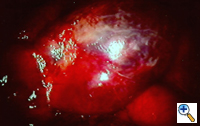

Group I: Single large bulla with normal underlying lung (Figure 1)

| Figure 1: Operative view at thoracotomy of a single bulla with normal underlying lung. | Figure 2: Operative view at thoracotomy of multiple bullae with underlying lung with diffuse emphysema. |